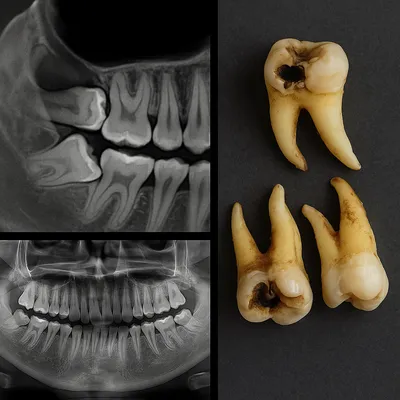

تصویربرداری: رادیوگرافی پانورامیک (OPG) دید کلی از دندانهای عقل، حفرهها و درگیری دندان آسیای دوم میدهد؛ در رویش کج، نیمهنهفته یا شک به درگیری ریشه و ضایعات عمقی، CBCT سهبعدی برای تعیین وسعت تخریب، ارتباط با کانال عصب و برنامهریزی درمان ضروری است.

اگر دسترسی مسواک سخت است، پلاک میکروبی مکرراً تشکیل میشود یا تورم موضعی دارید، ابتدا OPG و در موارد پیچیده CBCT انجام دهید؛ این رویکرد احتمال خطا را کم میکند و درمان هدفمندتری برای پوسیدگی دندان عقل رقم میزند.

عکس رادیوگرافی فک همراه با دندانهای انتهایی پوسیده و ریشههای غیرطبیعی